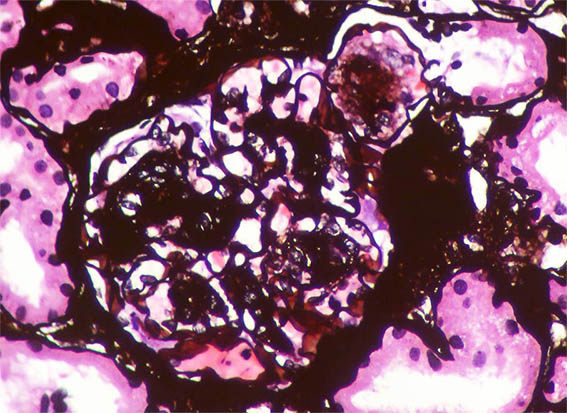

Figure 8. Methenamine-silver stain, X400.

Figure 10. Methenamine-silver stain, X400. Note the nodule on the upper right, surrounded by basement membrane (possibly microaneurysm with organizing thrombus).

Figure 12. Methenamine-silver stain, X1.000. The same nodule of figure 10; note "holes" in the basement membrane, on the left side.